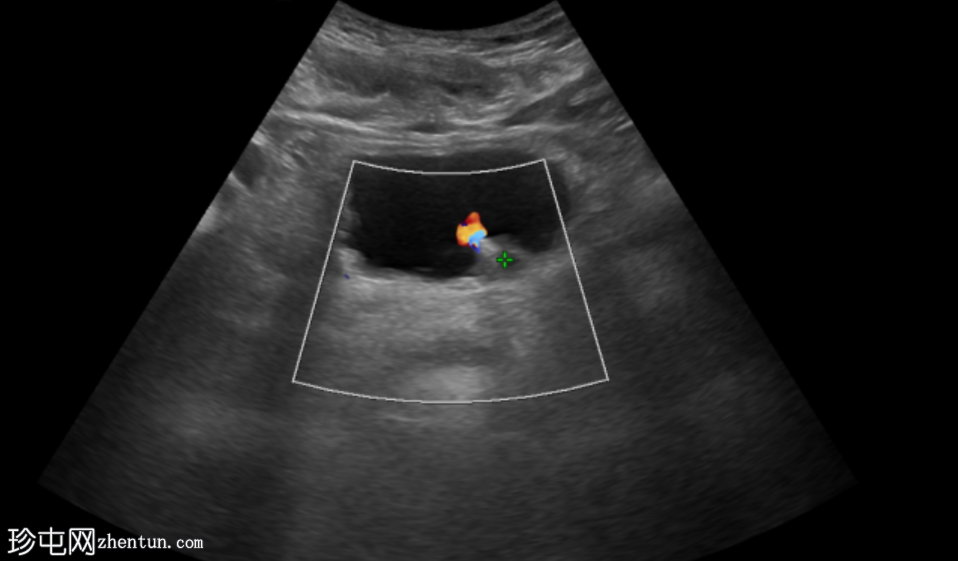

超声显示左侧轻度肾积水,由膀胱输尿管连接处一枚7毫米的远端输尿管结石阻塞所致,输尿管射流正常。

肾积水并非总是由输尿管结石引起。肾盂和肾盏扩张的程度与结石大小并不一定相关。

较小的结石有时可导致中度上游扩张,而较大的结石可能仅引起轻微的充盈感,这取决于患者的引流和水合状态。